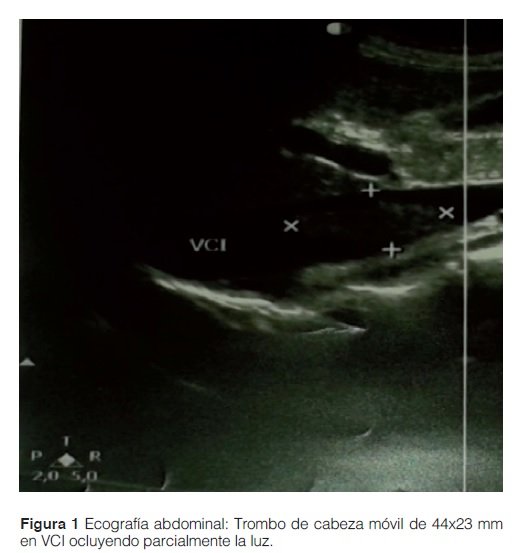

Se realizó una ecografía doppler donde se constató un trombo en la vena cava inferior flotante de 44 x 23 mm por encima de los vasos renales con oclusión parcial del ostium de la vena renal derecha. En la ecografía doppler de miembros no se objetivó datos de valor. En vista a estos resultados se decidió la anticoagulación con heparina de bajo peso molecular.

Como la paciente se encontraba con persistencia de taquicardia con ritmo sinusal en el electrocardiograma, se realizó una ecocardiografía donde se visualizó un trombo a 14 mm de la entrada de la aurícula derecha, por lo que se decidió realizar trombolísis en la Unidad de Cuidados Intensivos con rTPA (activador tisular del plasminógeno recombinante) sin complicaciones y con desaparición de todos los trombos en controles posteriores tal y como se observa en la tabla 3.